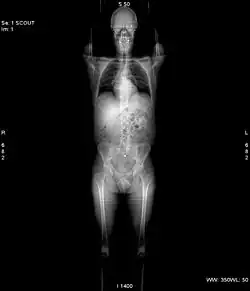

Picture of a CT scout (scanogram or topogram) as used for planning every scan slice.